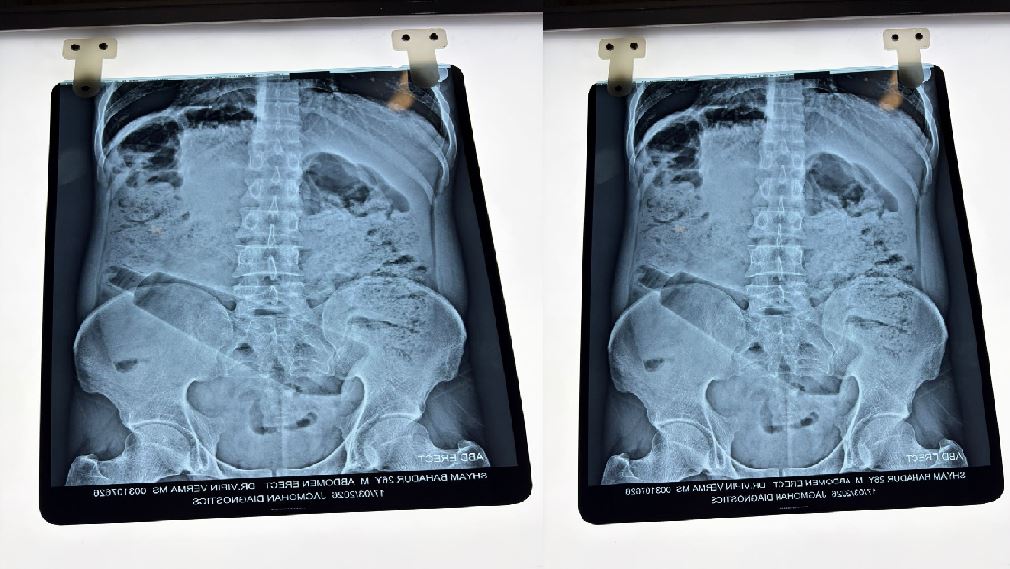

डॉक्टरों ने इस मामले में ऑपरेशन करके पेट से प्लास्टिक की बोतल निकाली है…बता दें कि इस तरीके का मामला कुछ दिन पहले आगरा से भी सामने आया था…जहां पर युवक ने अपने प्राइवेट पार्ट में बोतल डाल ली थी…